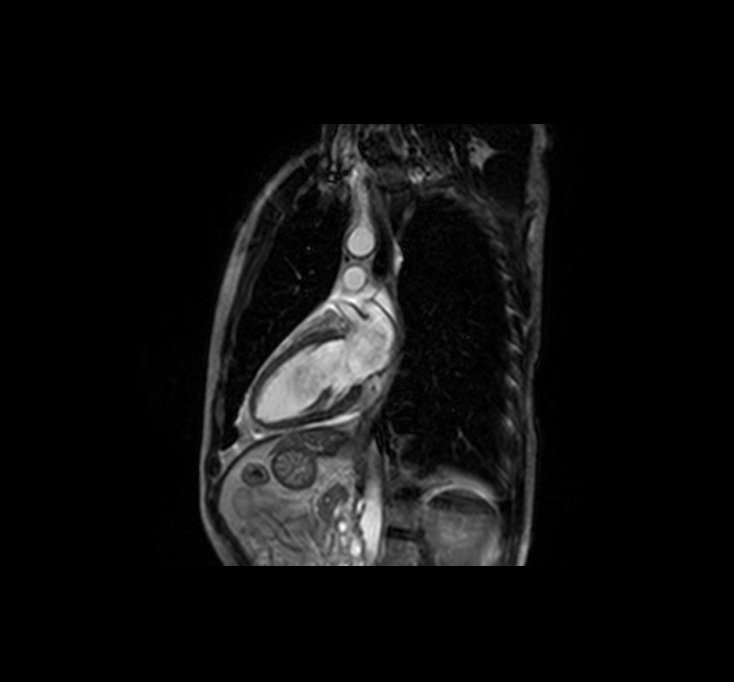

Heart MRI